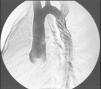

Presentamos el caso de un varón de 13 años de vida y 40kg de peso, remitido para tratamiento por diagnóstico de coartación de aorta y ductus. A la exploración física presentaba ligera hiperdinamia con un soplo continuo 2–3/6 infraclavicular izquierdo, asimetría en los pulsos y gradiente tensional entre miembros, con hipertensión en miembros superiores. El ECG mostraba crecimiento ventricular izquierdo y en la radiografía de tórax (fig. 1) se apreciaba ligera cardiomegalia con muescas costales (signo de Roësler). La ecocardiografía transtorácica demostró la presencia de una coartación aórtica severa a 25mm de la arteria subclavia izquierda con ligera hipoplasia de istmo aórtico, con dilatación poscoartación, y un ductus arterioso persistente yuxtacoartación de unos 2mm. Se realizó angioplastia primaria percutánea de la coartación con implantación de stent recubierto montado sobre balón de 18mm, que ocluye simultáneamente el ductus (fig. 2). Buen resultado angiohemodinámico, sin cortocircuito ductal residual, ni gradiente de presión aorta ascendente-descendente (fig. 3). Alta a las 24h del procedimiento con doble antiagregación.